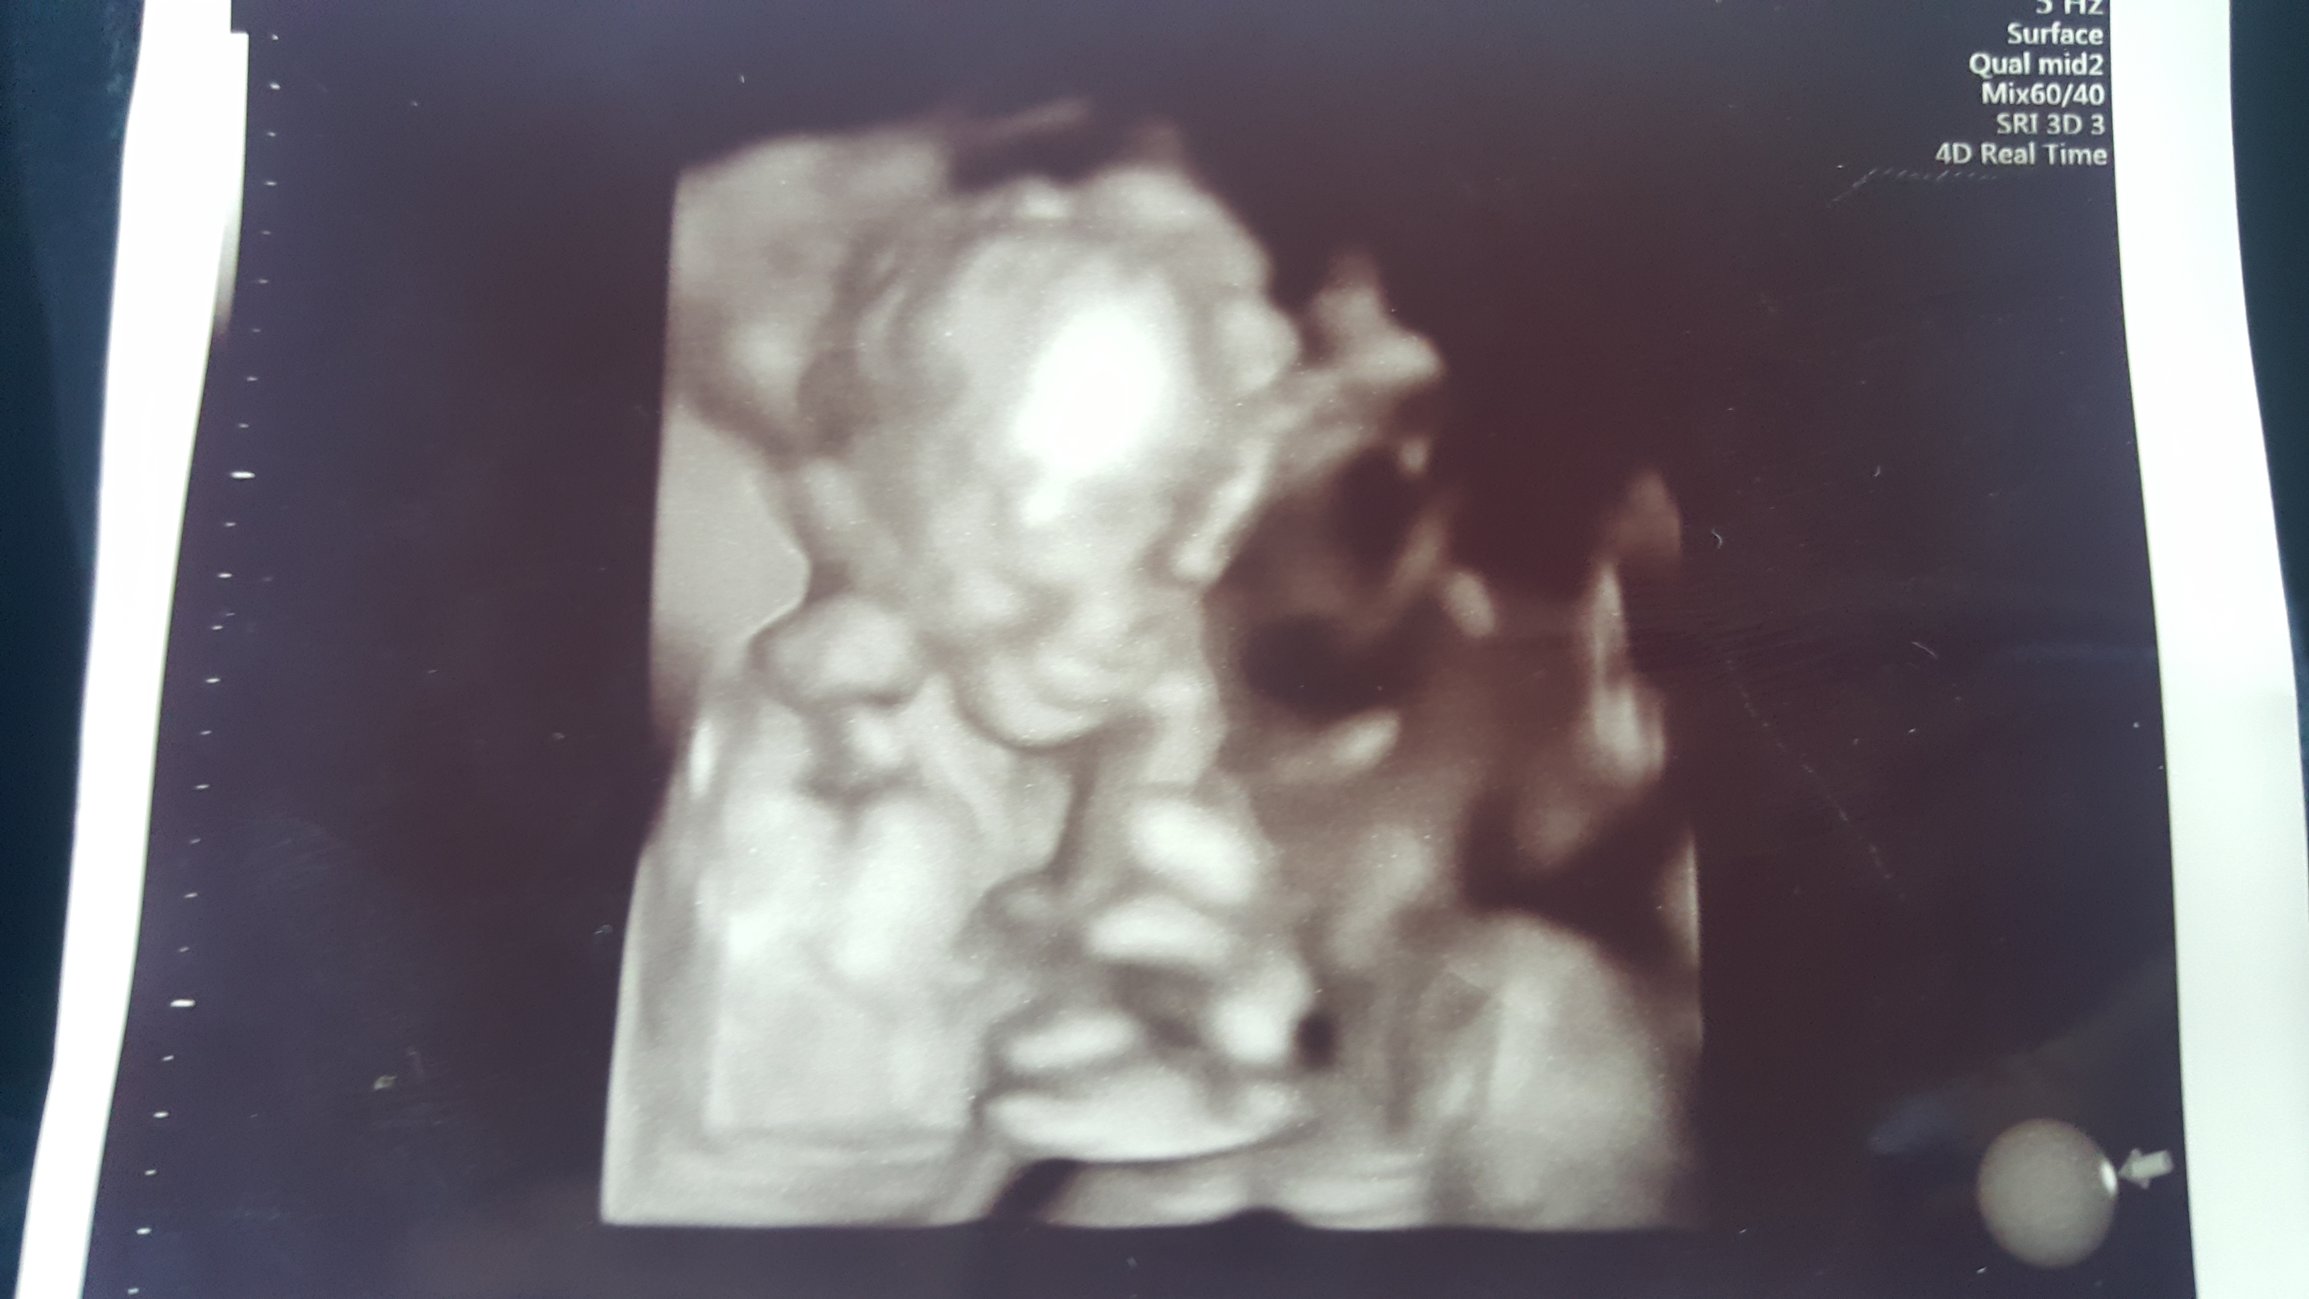

Re: Twin to Twin Transfusion Syndrome *TW*

BFP: 6/22/2016 EDD: 3/4/2017.